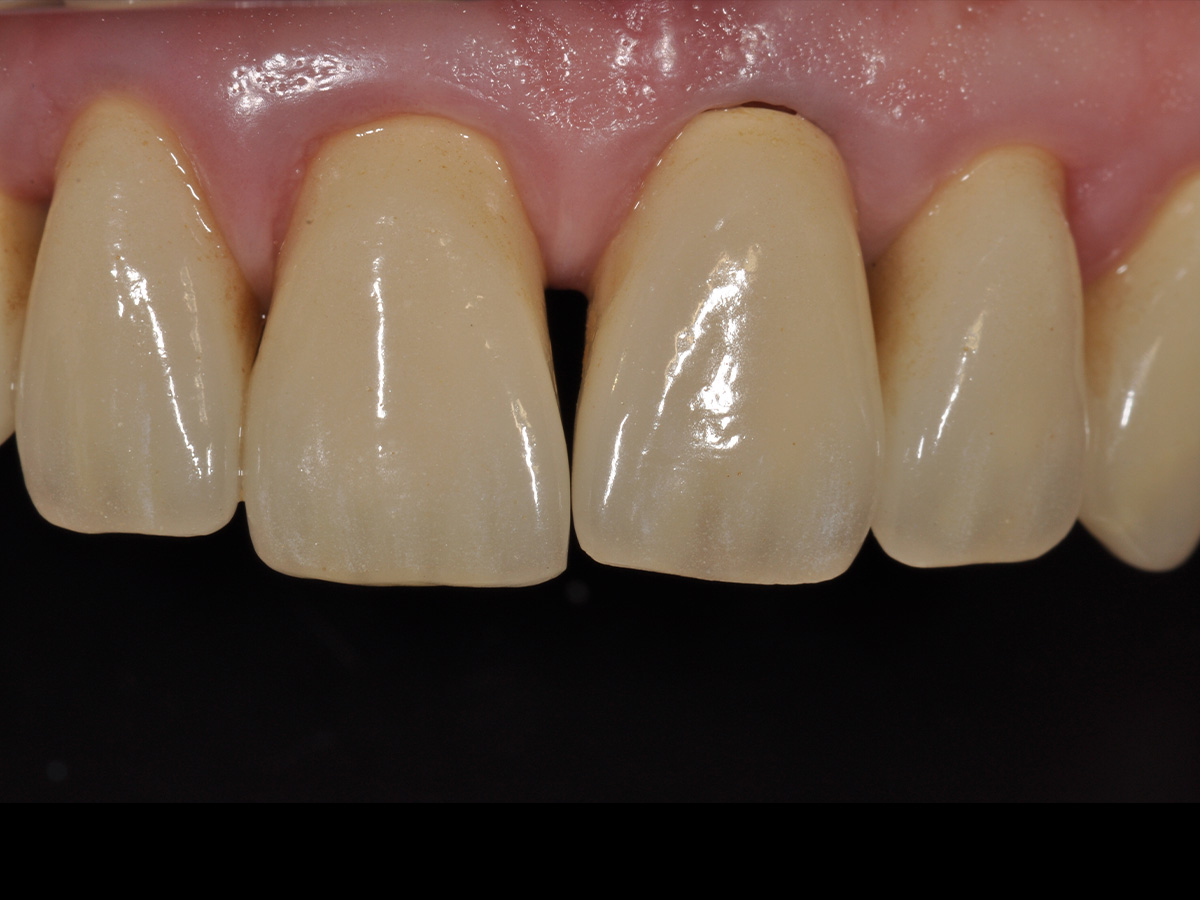

Abbildung 2

Klinische Ausgangssituation.